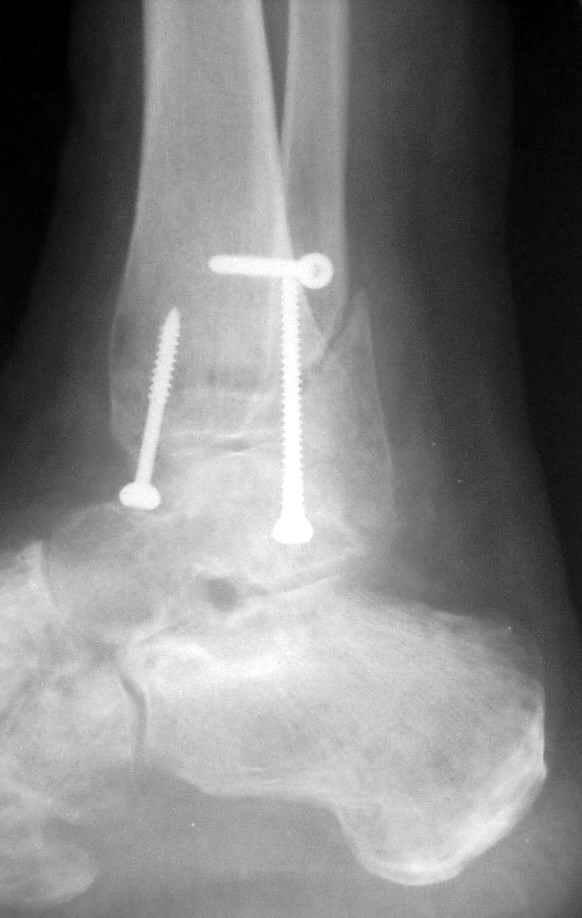

Ниже рентгенограммы

До операции 28 июля

Риторический вопрос - в каком руководстве рекомендован такой способ остеосинтеза наружной лодыжки?

Очевидно, такой результат операции был запрограммирован. При невосстановленной длине и практически нефиксированной малоберцовой кости (этот кортикальный винт - как карандаш в стакане), при неустраненном подвывихе, невправленной и тоже нефиксированной внутренней лодыжке нет стабильной вилки сустава. Если такую операцию сделать даже сразу, а не через 4 месяца, то результат ожидаем

тот же.

Вообще говоря, такое повреждение вполне успешно можно лечить без операции - если 6 недель подержать в гипсовом "сапожке" с хорошо устраненным подвывихом. Вероятное несращение внутренней лодыжки не обязательно компрометирует результат.

Ну а уж если выбран остеосинтез - нначать надо было с репозиции малоберцовой кости с точным восстановлением длины, с фиксацией треть-трубчатой пластиной по задней поверхности. Позиционный винт

избыточен - повреждение практически подсиндесмозное. А если бы

действительно было повреждение синдесмоза - в 4 месяца позиционный винт - не решение. Внутренню лодыжку такую - надо было бы спицами и проволочной петлей. Извините за эти банальности.